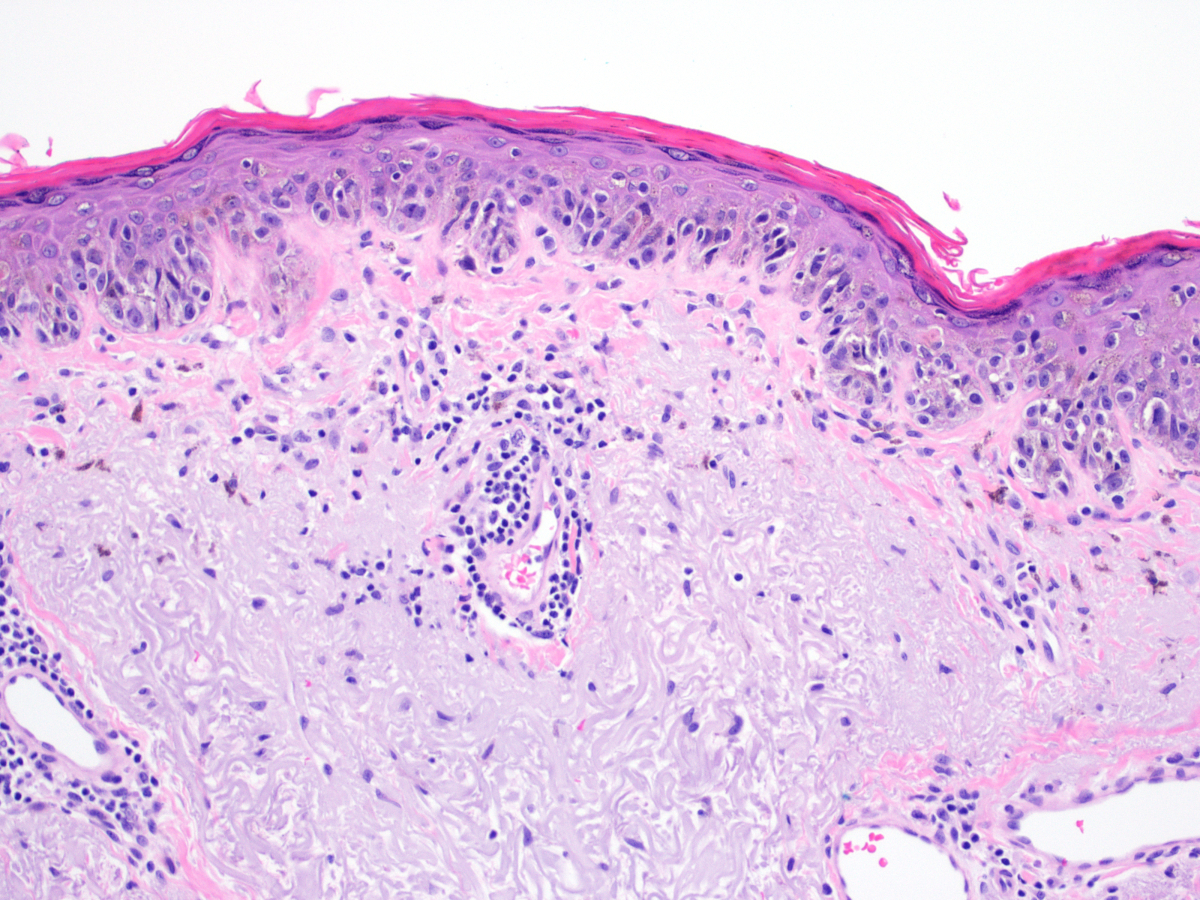

Melanoma (惡)

可以從 Melano cell, Naevus 轉過來,多變,甚至可以沒有 Pigmentation

Horizontal phase(Radial) → Vertical phase (Invasive)

Cutaneous melanoma

- 第三常見(<5%)的皮膚癌,但卻是皮膚癌中致死率最高的(75%)(第一常見為basal cell carcinoma,第二為SCC)

- 主因為 UV

Oral mucosal melanoma

- 原因不明

| Acral Lentiginous - | oral melanoma中最常見的類型 |

|

||